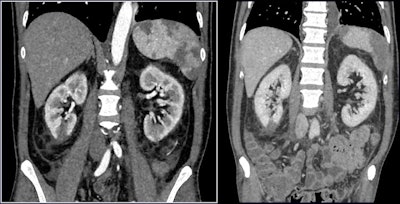

Imaging features of renal complications due to COVID-19 include renal parenchyma attenuation, perinephric fat stranding, and renal infarction (which can lead to vascular coagulopathy), presenter Prof. Riccardo Manfredi of the Gemelli University Hospital in Rome told session attendees. Manfredi also listed possible renal sequelae due to COVID-19, such as electrolyte dysfunction, acute kidney injury, and renal replacement therapy.

"Although imaging findings [of renal complications due to COVID-19] may not be specific, renal parenchyma attenuation and perinephric fat stranding can be detected on chest CT," he said. "And correlation [between imaging and] laboratory results can be a predictor of acute kidney injury."

- Keep the kidneys in mind when reading chest CT exams, since the organ is often visible on caudal images. Look for perinephric fat stranding and renal density on unenhanced CT studies.